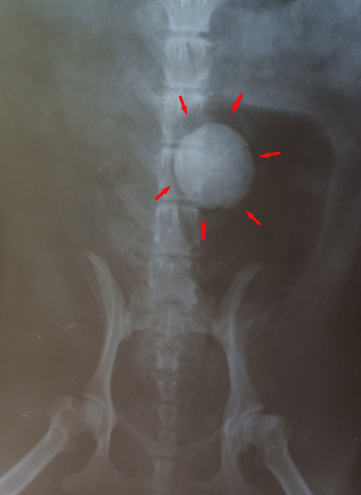

レントゲン検査(結石の有無、大きさを確認)

↑手術で取り除いた膀胱結石

結石が大きい場合や尿道を塞いでいる場合は、膀胱切開手術で取り除く